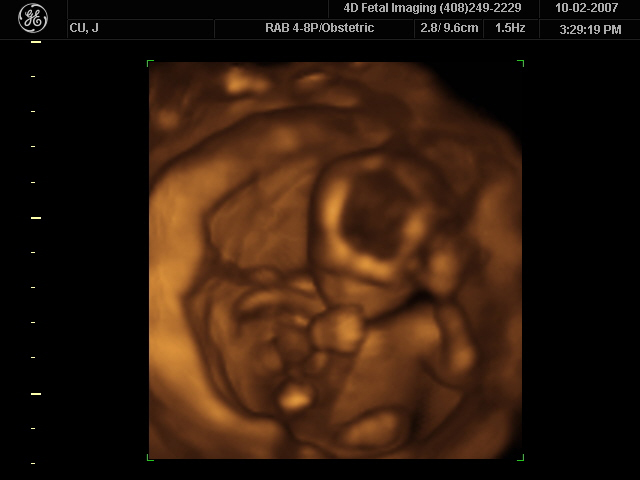

Figure 17.45 (a) An ultrasonic image is produced by sweeping the ultrasonic beam across the area of interest, in this case the woman’s abdomen. Data are recorded and

analyzed in a computer, providing a two-dimensional image. (b) Ultrasound image of 12-week-old fetus. (credit: Margaret W. Carruthers, Flickr)

How much detail can ultrasound reveal? The image in Figure 17.45 is typical of low-cost systems, but that in Figure 17.46 shows the remarkable detail possible with more advanced systems, including 3D imaging. Ultrasound today is commonly used in prenatal care. Such imaging can be used

to see if the fetus is developing at a normal rate, and help in the determination of serious problems early in the pregnancy. Ultrasound is also in wide

Figure 17.46 A 3D ultrasound image of a fetus. As well as for the detection of any abnormalities, such scans have also been shown to be useful for strengthening the

emotional bonding between parents and their unborn child. (credit: Jennie Cu, Wikimedia Commons)